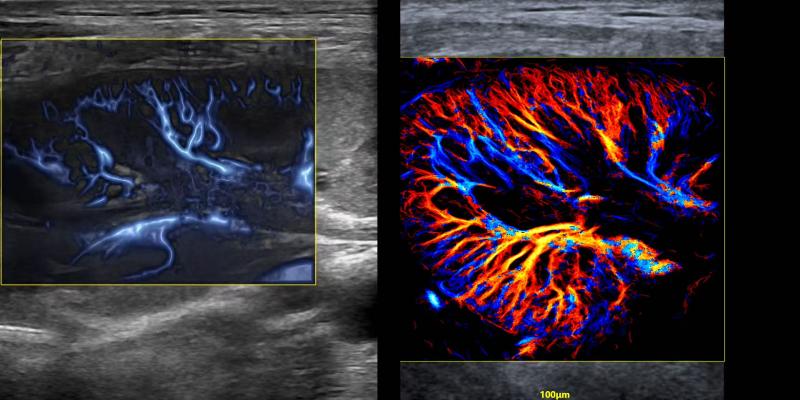

2024年、飛依諾はURM超高解像度の顕微畫像技術(shù)を開発したことを発表した。この技術(shù)は臨床と科學(xué)研究活動(dòng)にかつてない真新しい超音波の視野を切り開き、業(yè)界の専門家から「今後10年間に超音波業(yè)界で最も重要な技術(shù)的突破」と評(píng)価された。

現(xiàn)在、全國(guó)で100以上の三甲病院がこの製品を使用して臨床研究を行っている。さらに、ヨーロッパ、南米、アジアなど世界各地からのトップクラスの専門家は飛依諾と協(xié)力して関連する科學(xué)研究も行っている。